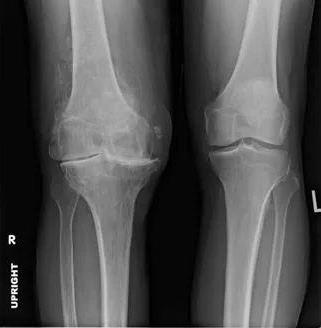

嚴重程度不同的骨關節炎,治療的方法是不一樣的,并不是所有的骨關節炎都需要手術治療,同樣,也并非所有的骨關節炎都可以通過藥物控制。比如下面同一個病人的兩個膝關節,病變處在不同的階段,接受的治療也不一樣。

x線下兩個膝關節的病變輕重明顯不同